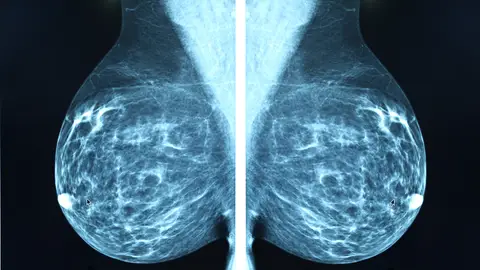

En España el cribado se hace mediante una mamografía cada dos años a todas las mujeres de 50 a 69 años, pero la oncóloga considera que debería modularse en función del riesgo alto, medio o moderado de cada persona, que en algunos casos puede no ser una cuestión de edad, sino de componentes genéticos heredados.

"Hay mujeres con muy alto riesgo de cáncer de hasta el 80 % por una mutación de un gen y a este grupo de mujeres hay que hacerles pruebas radiológicas frecuentes para detectar de forma precoz, pero para el resto, en función de si son de riesgo bajo o medio, a lo mejor no todas necesitan una mamografía cada dos años; igual unas cada año y otras cada tres", ha ejemplificado la doctora salmantina.

Así, consistiría en diversificar pruebas (a unas mujeres les bastaría una mamografía y otras requerirían una resonancia), ampliar el abanico de edad y ajustar las frecuencias de las pruebas, unos cambios que supondrían "una inversión brutal" pero que Rubio cree que es "el momento de empezar a plantearse que esto es lo que hay que hacer".